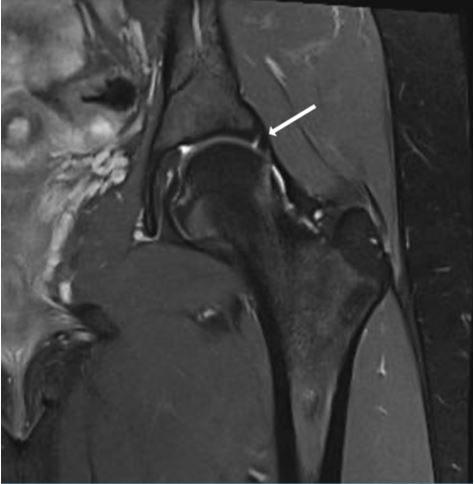

La resonancia magnética (Fig. 5) es fundamental en el contexto de PFA para diagnosticar posibles lesiones del labrum y determinar su localización16. También pueden ser visualizadas las lesiones del cartílago, como la delaminación asociada a deformidades tipo Cam. Este estudio es útil para valorar el estado de la articulación, ya que la presencia de edema subcondral indica sufrimiento articular, lo que generalmente se asocia con resultados no satisfactorios tras tratamiento quirúrgico artroscópico. Además, la resonancia magnética es de gran utilidad en el diagnóstico diferencial de otras patologías de cadera previamente mencionadas.

Figura 5. Resonancia magnética de cadera izquierda en corte coronal. Se observa una lesión del labrum indicada por la flecha